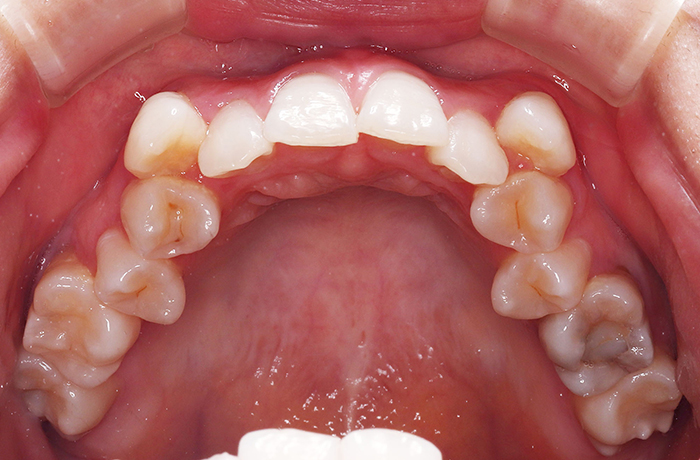

A様

治療前

before

年齢 31歳

性別 女性

治療名称 マウスピース型カスタムメイド矯正歯科装置(インビザライン)・コンプリヘンシブパッケージ(難症例)

総額治療費用 935,000円(税込10%) 金額備考 精密検査料・診断料 33,000円(税込10%)

治療期間 3年4か月 通院頻度など 1か月ごと(途中から3~4か月ごと)

患者の症状 叢生、正中のずれ、上顎左右側切歯の口蓋側転位(交叉咬合)

治療方法 非抜歯で、マウスピース型カスタムメイド矯正歯科装置(インビザライン)による矯正

歯列弓を拡大することで非抜歯を可能にしました。

治療結果 側切歯の交叉咬合は解消、上下正中のずれも改善し咬み合わせが良くなりました。